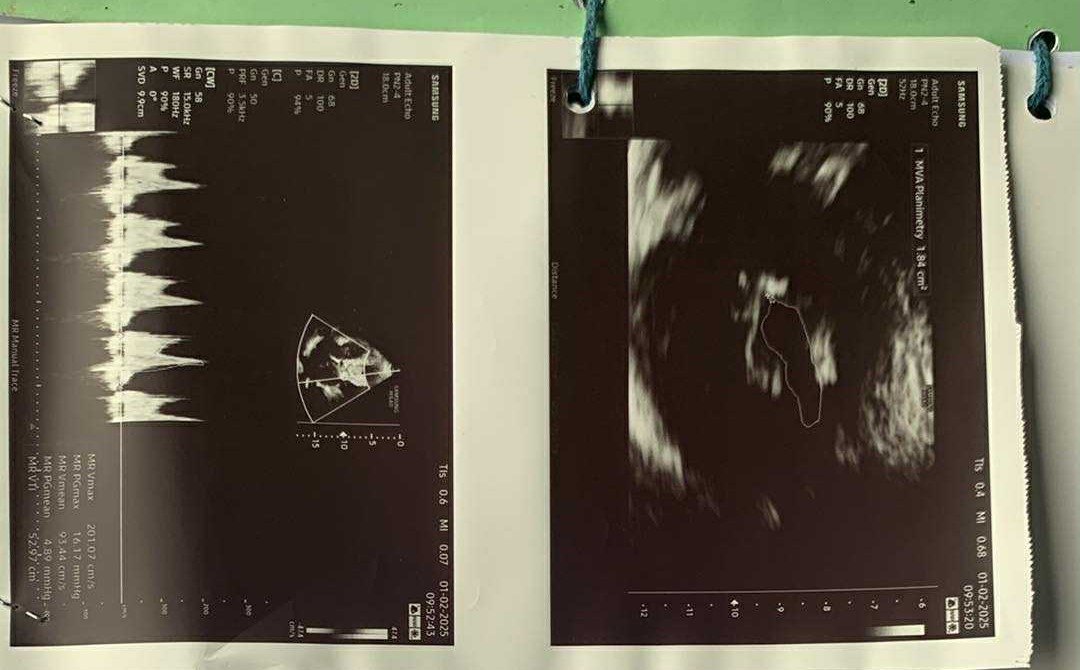

मुटुको अपरेशन गरि नियमित औषधी सेवन गरिरहेका खतिवडालाई नियमित उपचारका लागि कास्कीस्थित फिस्टेल अस्पतालमा राखिएको थियो ।